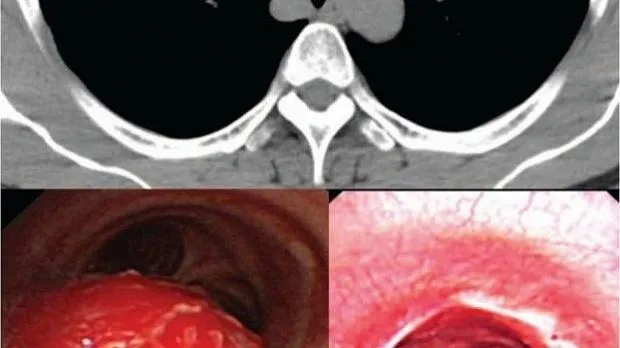

Что такое рак трахеи . Раковые новообразования в трахее развиваются нечасто . Они чаще встречаются у лиц мужского пола, чем у женщин, в 40-60 лет . У детей опухоли в большинстве (90%) случаев являются доброкачественными . Рак трахеи (код по Мкб10 — C33) обычно локализуется в нижнем . . .

Рак трахеи . Рак трахеи - достаточно редкое онкологическое заболевание, может быть первичным и вторичным . Первичный рак трахеи - злокачественный процесс начинается непосредственно в клетках органа, вторичный - результат прорастания/распространения опухоли из . . .

Плоскоклеточный рак трахеи, в отличие от такого же рака лёгкого, чуть менее злобный с не такими бурными темпами роста .